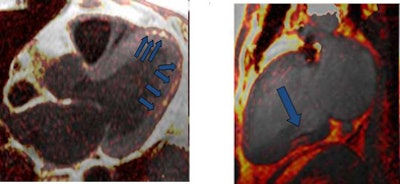

The study revealed foci of fat attenuation within the myocardium in 35 (64%) of 55 patients with TSC. Ranging in size from 3 x 1 mm to 62 x 31 mm, the fat was well circumscribed and focal. The majority of foci were found in the interventricular septum and left ventricle wall, with a few others in the right ventricle wall and papillary muscles.

"This location differs from intramyocardial fat in the right ventricle that has been described in healthy patients and in patients with arrhythmogenic right ventricular dysplasia (ARVD)," they wrote.

In addition, ARVD patients show a more diffuse fat infiltration as opposed to the focal mainly ovoid fatty foci seen in TSC patients in the study, they noted. No enhancing regions were seen in the fatty foci in TSC patients, in contrast to foci seen in patients with primary cardiac hemangioma.

| Myocardial fat in patient with tuberous sclerosis complex at CT. Image courtesy of Dr. Miraude Adriaensen. |

Only one individual in the control group (34-year-old woman) had a thin curvilinear hypoattenuated lesion in a subendocardial location, which might be suggestive of prior myocardial infarction.

"Despite incomplete depiction of the heart with CT, the majority of patients with TSC demonstrated well-circumscribed foci of fat attenuation in the myocardium that were not present in age- and sex-matched control subjects," Adriaensen and colleagues wrote. "This suggests that such fatty foci may be another characteristic of TSC."